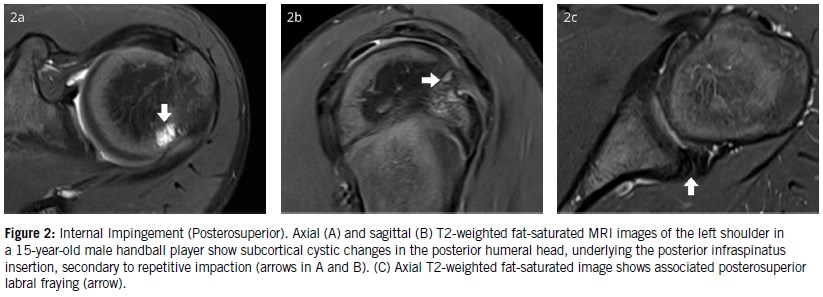

Posterosuperior impingement typically occurs in overhead athletes and results from repetitive tensile loading of the posterior shoulder capsule and the posterior band of the inferior glenohumeral ligament (IGHL). It is most evident during the late cocking phase of the throwing motion—just prior to forward arm acceleration.

Repetitive stress can lead to thickening and tightening of the posterior IGHL, altering normal shoulder mechanics and causing a posterosuperior shift of the humeral head when in the abducted and externally rotated (ABER) position¹. In this position, contact occurs between the undersurface of the rotator cuff and the posterior glenoid. Although this contact is physiological, when forceful and repetitive—as in overhead throwing—it may result in pathology.

MRI findings typically include articular-sided degeneration and tearing at the junction of the infraspinatus and supraspinatus tendons, in addition to degeneration or tearing of the posterosuperior glenoid labrum. Subcortical cysts and chondral lesions may also be present in the posterior glenoid or humeral head due to repetitive impaction (Figure 2).